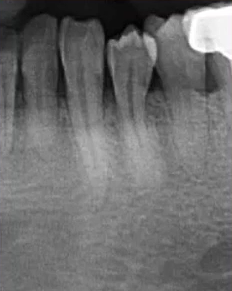

29岁,女性,自感牙体不适来院就诊

主要诊断:牙体——47龋坏伴根尖炎

牙列——35、45牙缺失,乳牙滞留,38、48智齿埋伏阻生

根尖片进一步诊断

47龋坏伴根尖炎

37继发龋!根尖炎?

25远中邻面浅龋